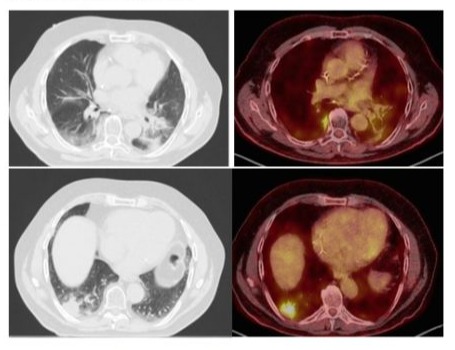

Finally, in the absence of any other side of tumor progression, the patient underwent a lobectomy with a mediastinal lymph node dissection and the pathology revealed a COP and no tumor (Figure 2).Following this results, pembrolizumab was interrupted after 15 cycles. The patient had no more any symptoms and did not receive any corticotherapy. One year later, a new progression occurred with lung, liver and adrenals metastases justifying starting pembrolizumab. Six months later, a PET-CT showed a partial response without any recurrence of the COP but an intense uptake in different mediastinal lymph nodes but with a negative EBUS.Three months later, a new PET-CT showed a complete metabolic response of the initial progressing lesions and an increase in FDG uptake at the level of mediastinal lymph nodes without morphological modification.

Figure 2: This high power view shows the typical branching appearance of the granulation tissue plugs and the mild interstitial inflammatory infiltrate.